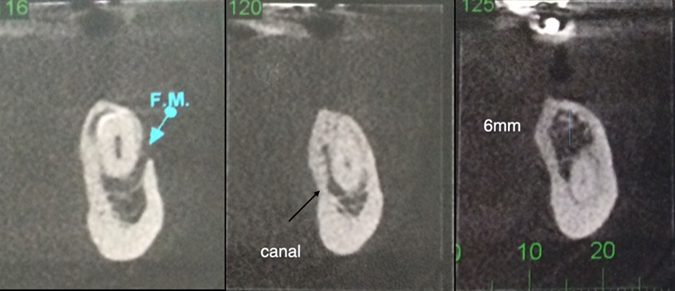

Case 1: a 37-year-old patient sought treatment with osseointegrated implants to replace a removable prosthesis in the posterior region of the mandible. In the imaging exams, a lower premolar was discovered included in the edentulous area (figure 1). After evaluation by an orthodontic specialist, traction was ruled out. In an evaluation using cone beam tomography, a close relationship was observed between the tooth and the inferior alveolar nerve from the crown to the apex, the nerve was embraced by the tooth (figure 2). When assessing the risk-benefit of tooth removal, the high chance of paresthesia was considered, in addition to a probable large height defect after tooth extraction.

Figure 2: Cone beam computed tomography showing the proximity of the mandibular canal to the root apex of the impacted premolar.